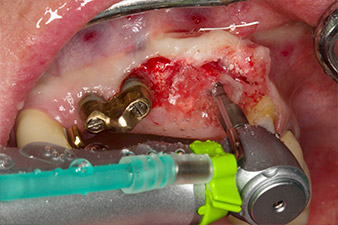

Taraudage avec le contre-angle WS-75 L

Fig. 3 : Taraudage avec le contre-angle WS-75 L suivant un ratio de 20:1 (programme P4). Le couple élevé de l'Implantmed, son système de serrage hexagonal pour une transmission de puissance fiable et l'inversion automatique du sens de rotation lorsque la résistance est trop élevée s'avèrent être des caractéristiques particulièrement utiles ici.